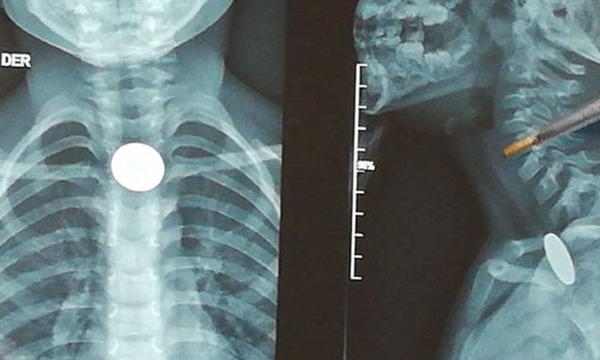

En solo una semana, el Instituto Nacional de Enfermedades Respiratorias y del Ambiente (Ineram) registró cuatro procedimientos de extracción de monedas en niños, una situación que encendió la alerta entre los especialistas y renovó el llamado a extremar cuidados en el entorno familiar. El neumólogo Dr. Carlos Morínigo explicó que los casos se presentaron en los primeros días del 2026 y que los pacientes llegaron de urgencia tras ingerir monedas de distintos valores. En ese sentido, detalló que se extrajeron una moneda de 1.000 guaraníes, una de 500 y dos de 100 guaraníes. Las intervenciones se realizaron a cuatro niños:… ...[Leer más]